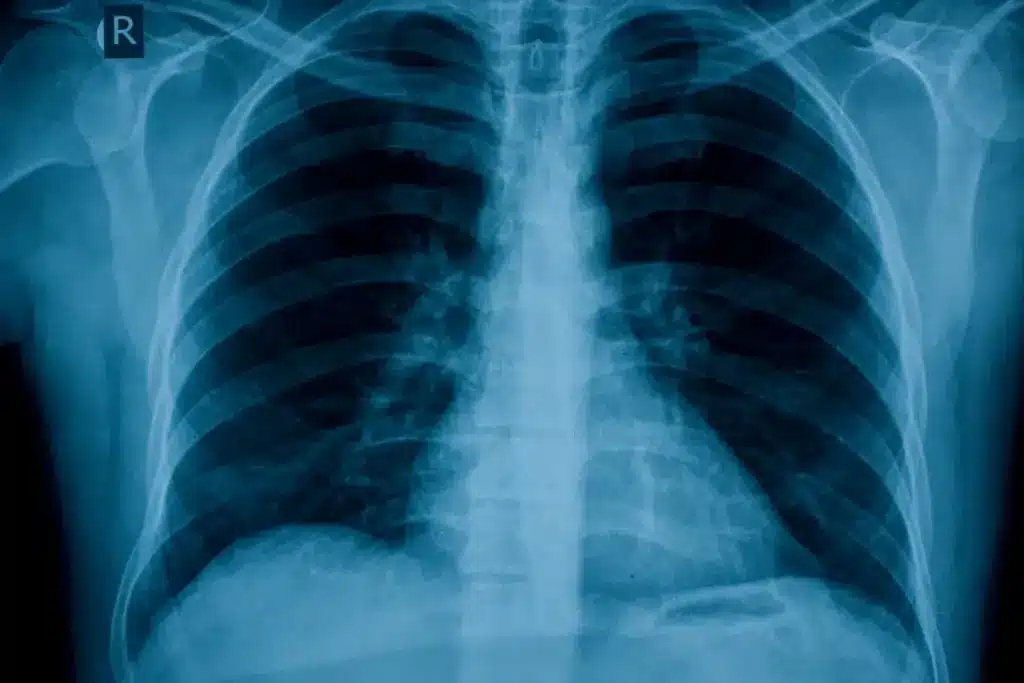

Bronchial wall thickening is diagnosed with chest X-rays and CT scans. These tools give important details about the bronchial walls. They help find the reasons for thickening.

Chest X-rays and CT Scan Findings

Chest X-rays are often the first step to check bronchial wall thickening. But, they might not show all the details. CT scans, with their higher resolution, can spot small changes in the bronchial walls.

CT scan findings can include:

- Thickness of the bronchial wall

- Extent of thickening along the bronchial tree

- Presence of other abnormalities such as bronchiectasis or nodules